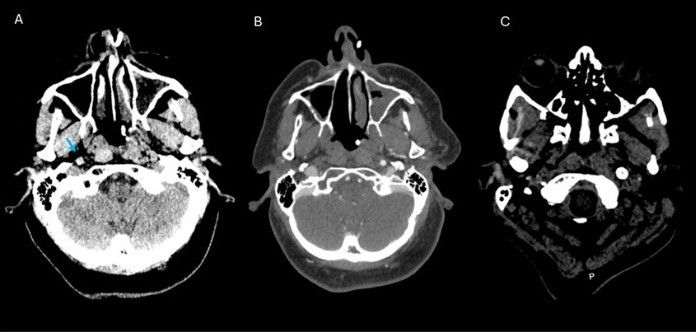

onlinelibrary.wiley.com/doi/10.1111/...

#neuroimaging #neurology #neuroskyence #radiology #chordoma #mri #review

onlinelibrary.wiley.com/doi/10.1111/...

#neuroimaging #neurology #neuroskyence #radiology #chordoma #mri #review